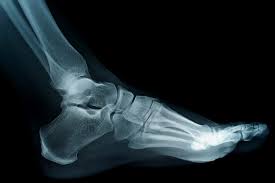

and ankle no one could describe as slender

till recently. Recovering from stumble

(I didn’t fall), I must have wrenched within.

Advancing age reminds me to be humble,

no matter what seems clear beneath my skin.